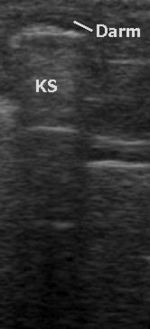

Zugänglichkeit von Organen

Alle wasserhaltigen, blutreichen Organe sind für den Ultraschall gut untersuchbar. Schlecht untersuchbar sind alle gashaltigen oder von Knochen bedeckten Organe, zum Beispiel der Darm bei Blähungen, die Lunge, Gehirn und das Knochenmark. Manche Organe sind im Normalzustand nur schwierig, im krankhaft vergrößerten Zustand dagegen gut erkennbar (Blinddarm, Harnleiter, Nebennieren).

Das Verfahren hat in tief gelegenen Geweben eine geringere Raumauflösung als die CT und MRT. Auch die Weichteil- Kontrastauflösung kann der bei der MRT unterlegen sein. Gas und Knochen verhindern die Ausbreitung der Ultraschallwellen. Daher ist die Sonografie bei gasgefüllten Organen (Lunge, Darm) und unter Knochen (Schädel, Rückenmark) erschwert. Anders als bei anderen bildgebenden Verfahren gibt es keine standardisierte Ausbildung. Daher bestehen große qualitative Unterschiede in den diagnostischen Fähigkeiten der Anwender.